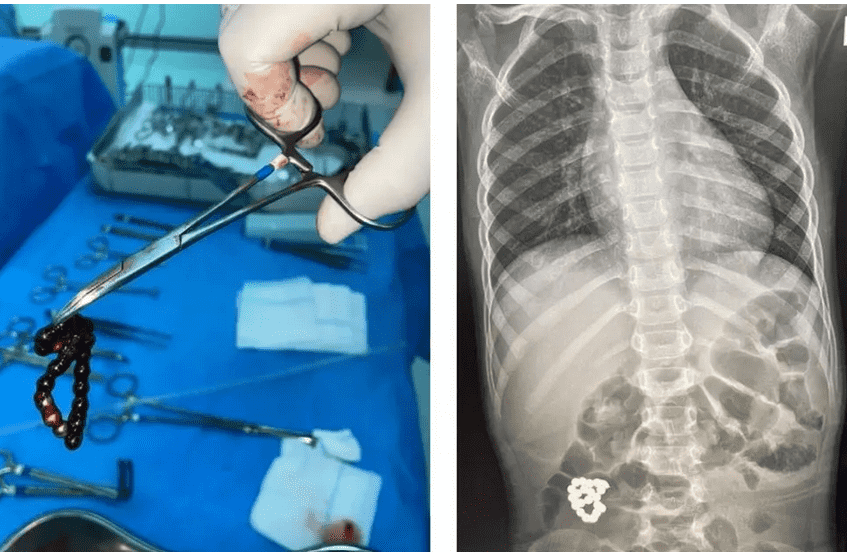

كما أضافت "أن الطفل حضر إلى طوارئ المستشفى يشتكي من آلام في البطن منذ 4 أيام، ازدادت مع الوقت، لتظهر صور الأشعة لاحقا وجود جسم غريب في أمعائه. وعلى الفور أدخل الصغير غرفة العمليات واستخرج الجسم الغريب، لافتة إلى أن جدار الأمعاء تضرر، لكنه الأطباء استأصلوا الأجزاء المتضررة بنجاح".